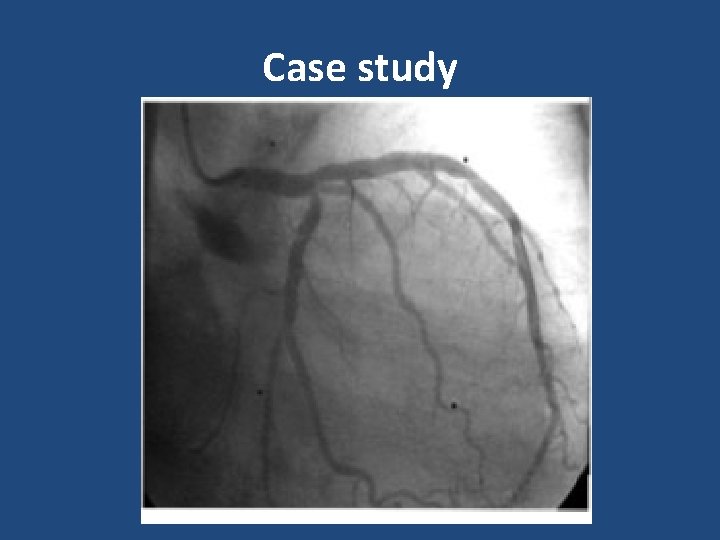

Case study